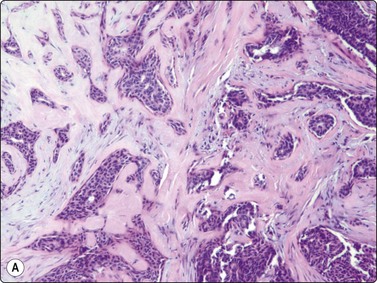

image image

Fig. 7.2 Non-neoplastic glandular breast tissue and low-grade duct carcinoma

Low-power view; (A) Bimodal population of epithelial sheets and single bipolar nuclei of non-neoplastic glandular breast tissue; (B) Single population of epithelial cells in low-grade carcinoma (MGG, LP).

Fig. 7.3 Non-neoplastic glandular breast tissue and low-grade duct carcinoma

High-power view, air-dried smears; (A) Non-neoplastic glandular breast tissue; (B) Low-grade duct carcinoma. Note single bipolar nuclei in A, and absence of bipolar nuclei, relatively mild nuclear atypia and some loss of cohesion of malignant cells in B (MGG, HP).

Fig. 7.4 Non-neoplastic glandular breast tissue and low-grade duct carcinoma

High-power view, Pap-stained smears; (A) Bimodal population in smear from non-neoplastic breast; (B) Single and clustered cells in low-grade carcinoma; some single cells probably stromal (Pap, HP).